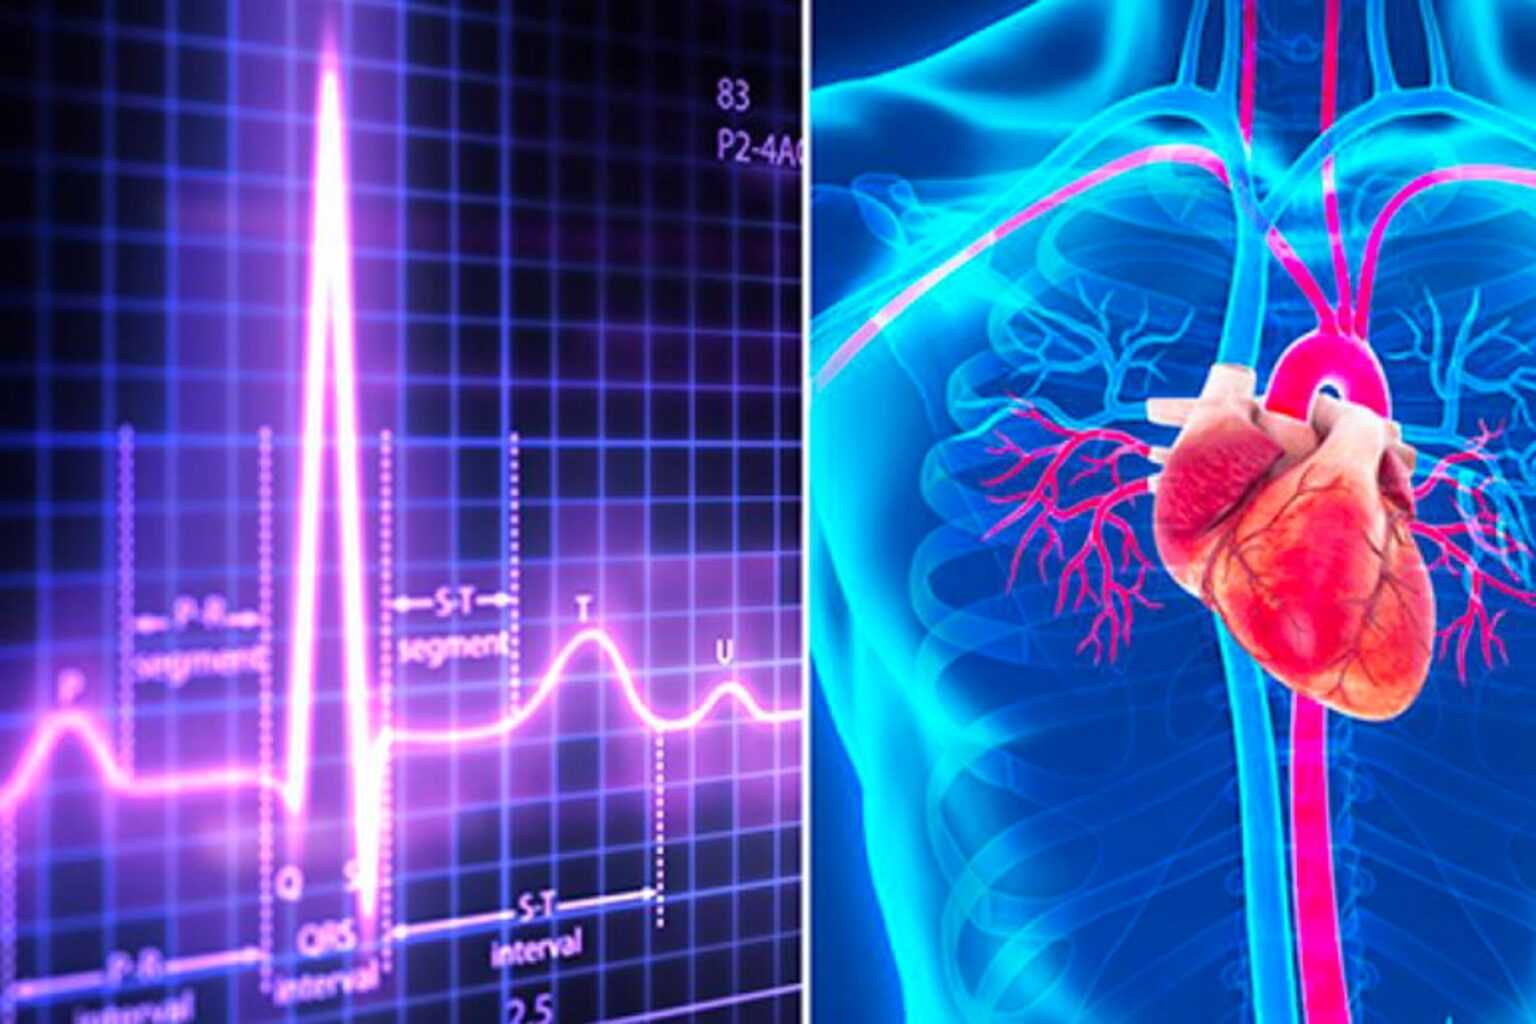

Η τροπονίνη είναι μια πρωτεΐνη που απελευθερώνεται στην κυκλοφορία του αίματος κατά τη διάρκεια μιας καρδιακής προσβολής. Η ανίχνευση της τροπονίνης στο αίμα μπορεί να βοηθήσει τους γιατρούς να διαγνώσουν καρδιακή προσβολή. Η καρδιακή προσβολή προκαλείται από τη ρήξη πλάκας μέσα σε μία από τις στεφανιαίες αρτηρίες σας, οδηγώντας σε σχηματισμό θρόμβου αίματος γύρω της. Αυτό εμποδίζει την παροχή αίματος στον καρδιακό μυ, ο οποίος καταστρέφεται λόγω έλλειψης οξυγόνου, εκτός εάν το πρόβλημα αντιμετωπιστεί άμεσα. Παράλληλα, η ανίχνευση της τροπονίνης στο αίμα μπορεί να βοηθήσει τους γιατρούς να διαγνώσουν καρδιακή προσβολή και να σας δώσουν τη θεραπεία που χρειάζεστε το συντομότερο δυνατό.

Λόγω της ανώτερης ευαισθησίας και ειδικότητάς τους σε σύγκριση με άλλους βιοχημικούς δείκτες, οι καρδιακές τροπονίνες είναι οι καλύτεροι δείκτες για την αναγνώριση της βλάβης των κυττάρων του μυοκαρδίου. Εξαιτίας αυτού, η καρδιακή τροπονίνη (cTn) είναι ο μόνος καρδιακός δείκτης που αναφέρεται στον καθολικό ορισμό του MI4 και χρησιμοποιείται μεμονωμένα στους πιο πρόσφατους επικυρωμένους τυποποιημένους κανόνες απόφασης για την αξιολόγηση του ACS.20,21 Δύο ειδικές για το μυοκάρδιο πρωτεΐνες, μυοκαρδιακή Η τροπονίνη Ι (TnI) και η τροπονίνη Τ (TnT), προηγούνται της απελευθέρωσης της κινάσης της κρεατίνης (CK-MB) στον ορό. Οι καρδιακές τροπονίνες είναι γενετικά διαφορετικές από τις μορφές τροπονίνης που βρίσκονται σε άλλους μυϊκούς ιστούς. Οι TnI και TnT είναι πολύ παρόμοιες ως προς τη διαγνωστική και προγνωστική τους αξία και την κινητική τους στον ορό και τα ποσοστά αύξησης και μείωσης που σχετίζονται με ισχαιμία του μυοκαρδίου, έμφραγμα και ACS.

Η βιοκινητική της απελευθέρωσης τροπονίνης σχετίζεται με τη θέση της πρωτεΐνης μέσα στο κύτταρο. Κανονικά, μικρές ποσότητες τροπονινών είναι ελεύθερες στο κυτταρόπλασμα, και οι περισσότερες περιπλέκονται στις μυϊκές ίνες. Μετά τον τραυματισμό, μια διφασική αύξηση των επιπέδων τροπονίνης ορού αντιστοιχεί σε πρώιμη απελευθέρωση των ελεύθερων κυτταροπλασματικών πρωτεϊνών, ακολουθούμενη από μια πιο αργή και πολύ παρατεταμένη άνοδο, με διάσπαση της πραγματικής μυϊκής ίνας. Η αργή καταστροφή των συσταλτικών πρωτεϊνών των κυττάρων του μυοκαρδίου παρέχει μια παρατεταμένη απελευθέρωση των τροπονινών για 5 έως 7 ημέρες. Τα επίπεδα της τροπονίνης στον ορό αρχίζουν να αυξάνονται μετρήσιμα στον ορό περίπου την ίδια στιγμή που γίνονται ανιχνεύσιμες οι αυξήσεις των επιπέδων CK-MB, ήδη από 2 έως 3 ώρες μετά την έναρξη, αλλά τα επίπεδα τροπονίνης παραμένουν υψηλά για 7 ημέρες ή περισσότερο.

Οι ειδικές για την καρδιά τροπονίνες, που προσδιορίζονται σειριακά, είναι εξαιρετικά ευαίσθητες για την έγκαιρη ανίχνευση τραυματισμού του μυοκαρδίου. Ένα θετικό αποτέλεσμα του τεστ σχετίζεται με σημαντικό κίνδυνο και τα αρνητικά σειριακά αποτελέσματα προβλέπουν χαμηλό κίνδυνο. Ωστόσο, μια μεμονωμένη μέτρηση τροπονίνης κατά την παρουσίαση έχει περιορισμένη αξία στον αποκλεισμό του ΑΜΙ στις πρώτες ώρες έναρξης των συμπτωμάτων και δεν έχει ικανότητα ανίχνευσης UA χωρίς έμφραγμα επειδή απαιτείται κυτταρικός τραυματισμός. Σειριακές μετρήσεις, ιδιαίτερα όταν εκτελούνται τουλάχιστον 6 ώρες μετά την έναρξη των συμπτωμάτων (ακόμη και 2-3 ώρες όταν χρησιμοποιούνται νεότερες, υψηλής ευαισθησίας δοκιμές), βελτιώνουν σημαντικά την ευαισθησία των καρδιακών τροπονινών για ΑΜΙ και το μοτίβο της ανόδου μπορεί να βοηθήσει στον προσδιορισμό της οξύτητας του συμβάντος.